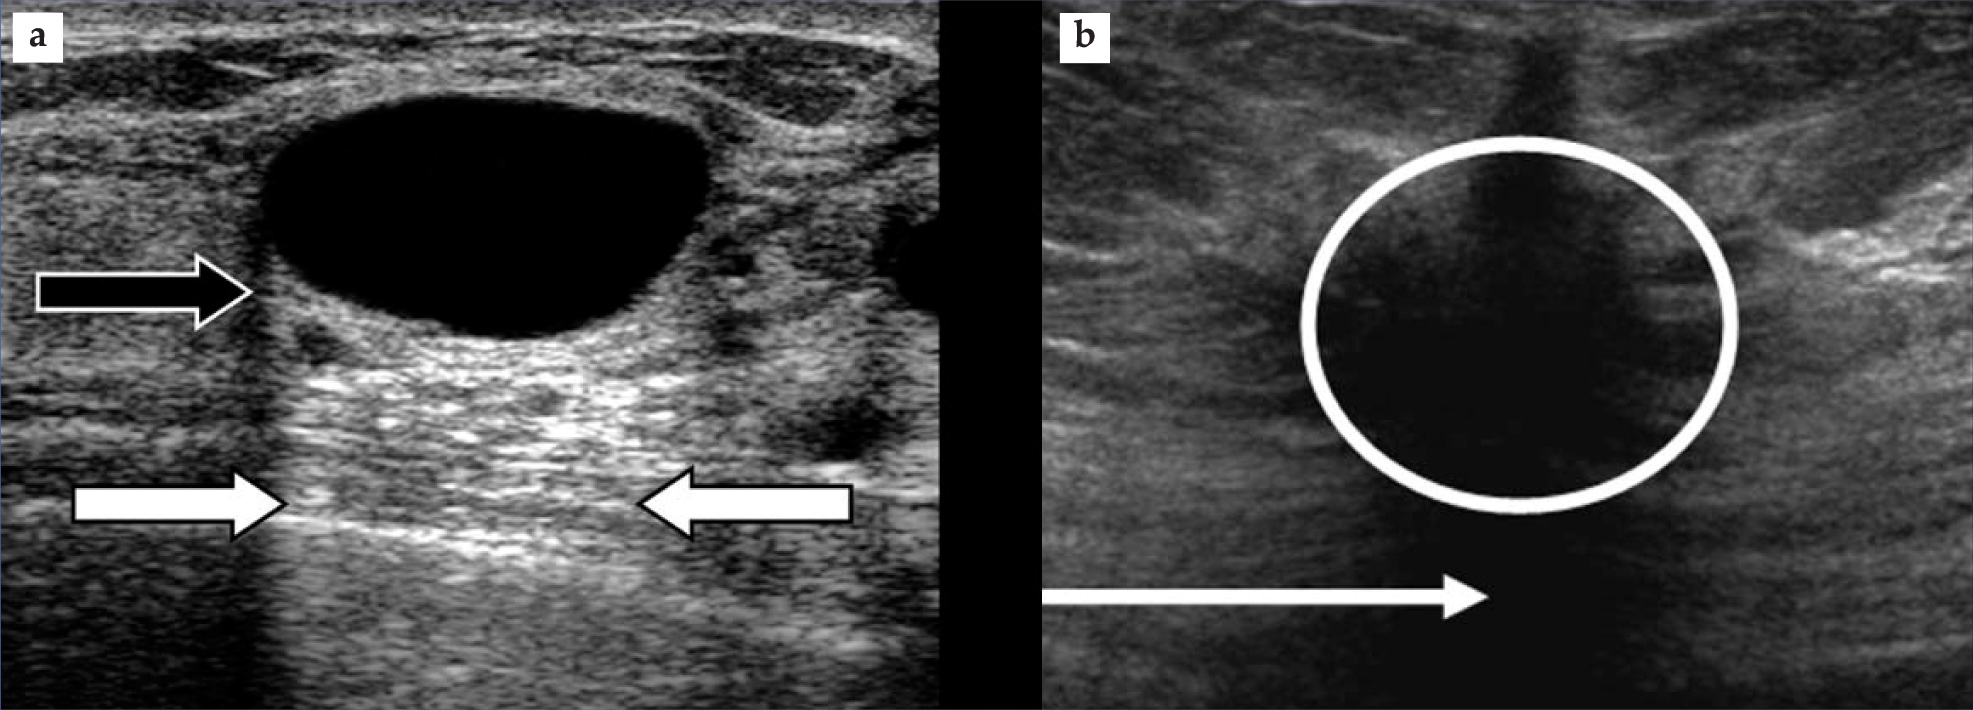

Published research suggests that the absorption occurs primarily at the molecular level. Most often, attenuation-related artifacts arise when the scattering strength and attenuation of an object are either both high or both low. The first case yields an artifactual shadowing, or echo weakening, that lies behind the object and that may be helpful in identifying high-attenuation structures such as stones, bones, and calcified abnormalities. The second case leads to echo strengthening behind the object, manifested as a brightening. That so-called enhancement helps identify cystic abnormalities; figure 1(a) furnishes an example. Less common are the cases of weak scattering, or hypoechogenicity, with shadow (but see figure 1(b)) and hyperechogenicity with enhancement.

Figure 1. Attenuation artifacts. (a) Visible in this breast image are an anechoic cyst (black region) and enhancement (between white arrows). Note, as well, a shadow emanating from the edge of the cyst (black arrow). The shadow arises because refraction at the cyst’s edge causes beam spreading that reduces beam intensity and thus weakens the echoes. (b) This breast image shows a hypoechoic carcinoma (circled) and a shadow (arrow). Two characteristics help to identify the structure as a carcinoma and not a cyst. First is the ragged edges around the lesion and second is the shadow, which contrasts with the enhanced brightness seen in panel a.

(Images courtesy of Philips Ultrasound.)